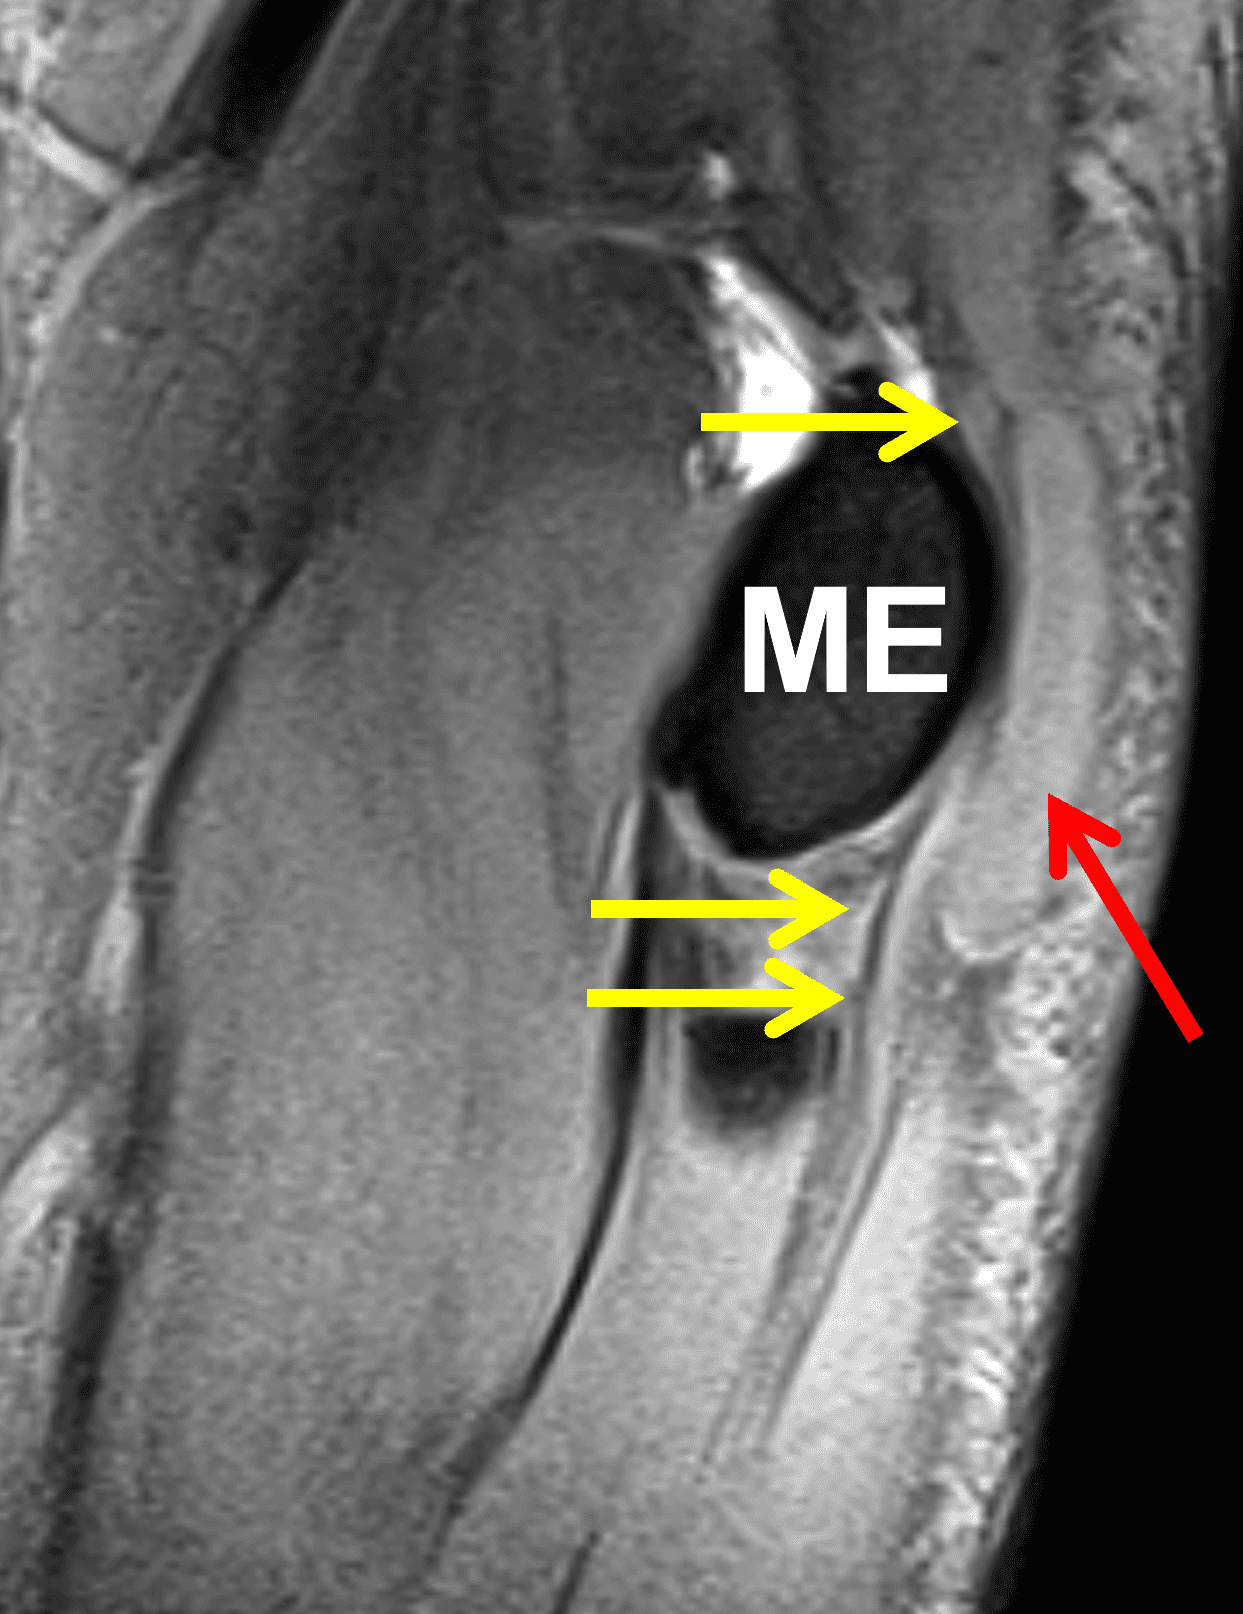

Figure 10: 32-year-old man with a post-traumatic neuroma that developed following an ulnar nerve laceration. Axial (10A) T1-weighted and (10B) fat-suppressed, fluid-sensitive sequences demonstrate enlargement and disorganized architecture of the ulnar nerve (arrows) proximal to the cubital tunnel. (10C) On a sagittal fat-suppressed, fluid-sensitive image, no nerve fibers are visible posterior to the medial epicondyle (ME) in the cubital tunnel (yellow arrow), the site of the nerve transection. The post-traumatic neuroma (red arrow) involves the proximal nerve stump. (10D) An axial fat-suppressed, fluid-sensitive image in the proximal forearm shows subacute denervation with the flexor digitorum profundus muscle (asterisk).